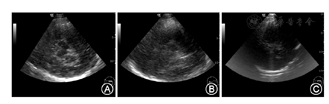

(1)声窗条件评估:TCS检查是经过颞骨的声窗完成,声窗条件好坏对检查能否成功至关重要,因此,首先评价声窗情况。声窗条件分为声窗良好、声窗欠佳和透声不良3种情况(图3)。